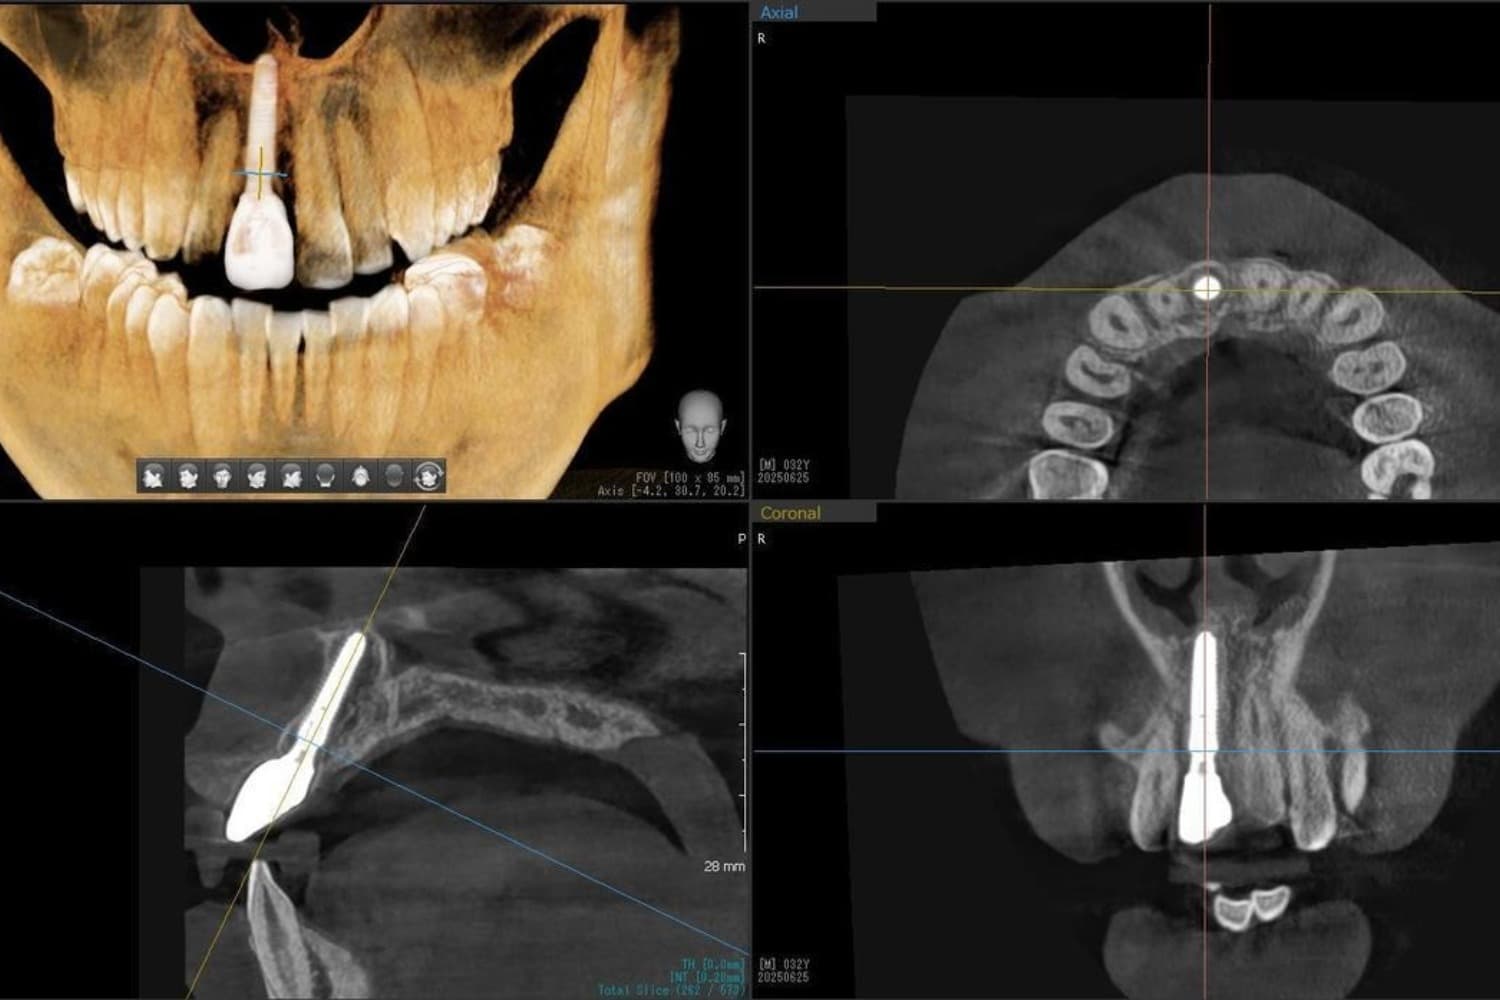

歯根破折した前歯のインプラント治療(30代男性)

Before

外傷によって歯根破折した前歯を抜歯してインプラント治療をおこなう(当日に仮歯の装着までおこなう)。

年齢

30代

性別

男性

主訴

外傷によって歯根破折している。

治療期間

2ヵ月半

治療回数

6回

費用

385000円(税込) 費用の内訳: 【インプラント基本料】330000円(税込み) 基本料金に以下を含む ・フィックスチャー及び手術費用 ・投薬費用、 ・レントゲン費用 ・インプラント上部費用(アバットメントおよびジルコニアクラウンの費用用) 【オプション費用】 ・抜歯即時埋入・即時負荷加算(プロビショナルレストレーション費用・人工骨費用・暫間アバットメント費用・抜歯費用を含む)55000円(税込)

副作用・リスク

・手術後に痛み・腫れ・出血・合併症等を引き起こす恐れがあります。 ・噛む感覚がご自身の歯と異なることがあります。 ・見た目がご自身の歯と異なる場合があります。 ・手術後もメインテナンスを続けないと、インプラントが抜け落ちてしまう恐れがあります。